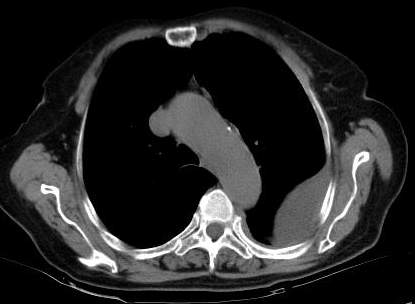

标题: CT0563:病历讨论,胸膜间皮瘤?

测ct值3-6hu,

既然ct值是3-6hu,还不如考虑包裹性积液。

请上传纵隔窗。目前还是支技包裹性积液(明显梭形),即使是间皮瘤并积液也少梭形的。

从图片看,包裹性积液好象更合理,梭形,ct值3-5hu(在哪看到的?);胸膜间皮瘤如此规则,不多见。

左侧背部胸膜肥厚,伴包裹性积液,不考虑间皮瘤.

同意以上各位的高见,首先考虑包裹性积液,1.胸膜间皮瘤积液量一般较大,以游离性积液更为常见,2.可以看到增厚的胸膜结节